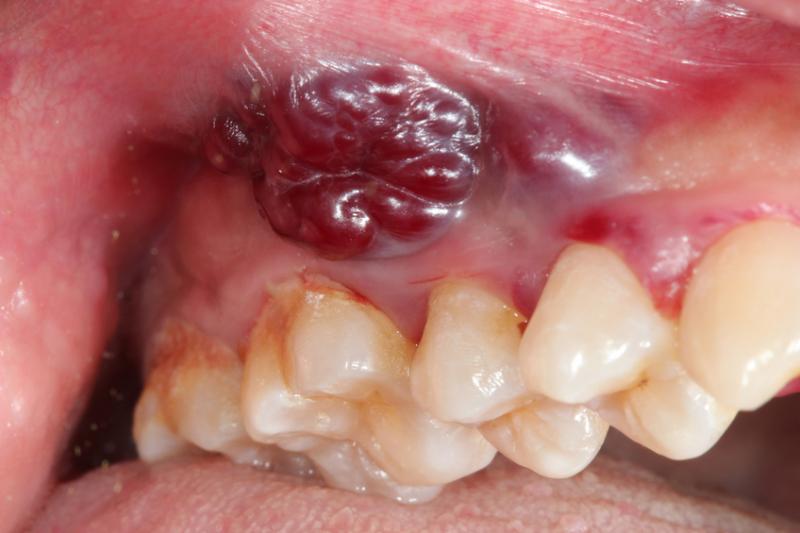

Καρκίνος στόματος εμφανίζεται, συνήθως, στα πλάγια ή στο κάτω μέρος της γλώσσας ή στο έδαφος του στόματος. Να θυμάστε, ότι οι όγκοι δεν προκαλούν πόνο και είναι ορατοί και ψηλαφητοί. Η τακτική εξέταση των μαλακών ιστών του στόματος είναι σημαντική για τον έγκαιρο εντοπισμό του καρκίνου του στόματος. Αν παρατηρήσετε κάποια επίμονη αλλαγή στην όψη ή στην αίσθηση των μαλακών ιστών του στόματος συμβουλευθείτε τον γιατρό σας. Ο έγκαιρος εντοπισμός παίζει μεγάλο ρόλο στην επιτυχημένη θεραπεία. Όταν ο καρκίνος στόματος εντοπισθεί στην αρχή με την τακτική αυτοεξέταση του στόματος και της γλώσσας η θεραπεία θεωρείται δεδομένη.